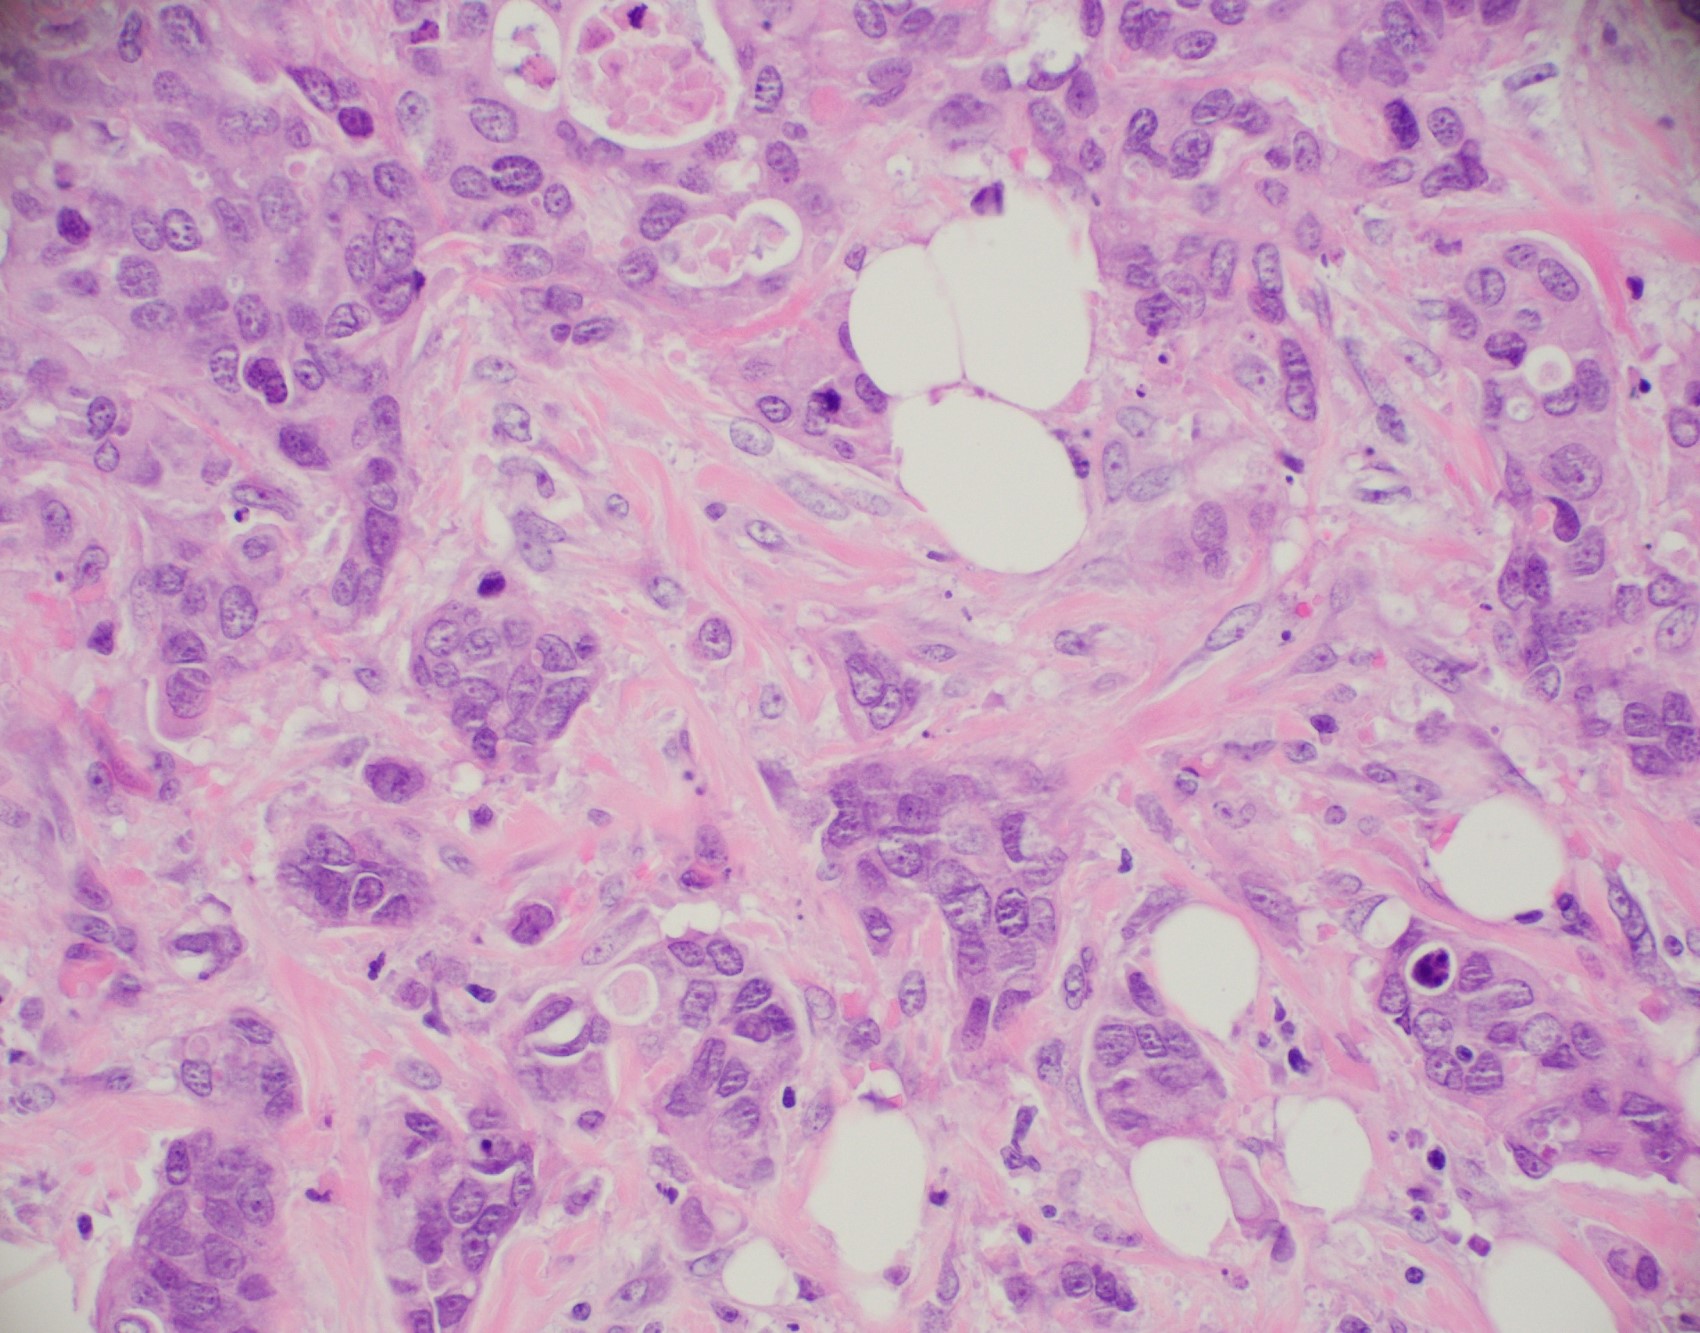

Microscopic (histologic) description

- Histological features of IBC NST vary considerably from case to case and even within the same case

- Architecture varies from sheets, nests, clusters, cords or individual cells (but lacks the cytomorphological characteristics of invasive lobular carcinoma)

- Tubular formations are prominent in well differentiated tumors but absent in poorly differentiated tumors

- Variable cytological features:

- Cytoplasm may be abundant and eosinophilic but it can show other features in some tumors, including as clear, foamy or granular

- Nuclei may be regular and uniform or highly pleomorphic with prominent or multiple nucleoli

- Calcification in 60% of cases, variable necrosis

Microscopic (histologic) images

Contributed by Julie M. Jorns, M.D., Kristen E. Muller, D.O., Gary Tozbikian, M.D. and Emad Rakha, M.D.